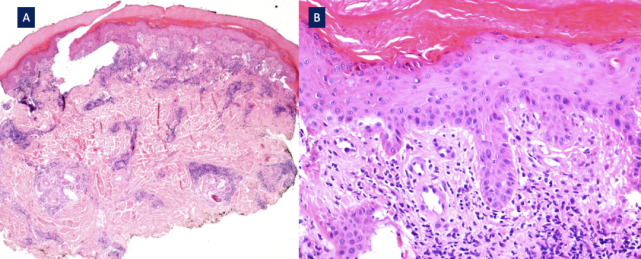

对右第三足趾溃疡性皮损进行环钻活检,病理示表皮浅层散在坏死(凋亡)角质形成细胞,基底层空泡样改变,真皮淋巴细胞呈苔藓样浸润,并累及血管周围和小汗腺周围,偶可见浆细胞(图5)。基底膜带模糊,可见少许核碎裂,未见中性粒细胞。真皮乳头无苍白、水肿,血管腔内未见纤维蛋白血栓,小静脉壁内未见纤维蛋白。直接免疫荧光阴性。

图片

图5. 足部紫红色斑块组织病理表现(引自参考文献)